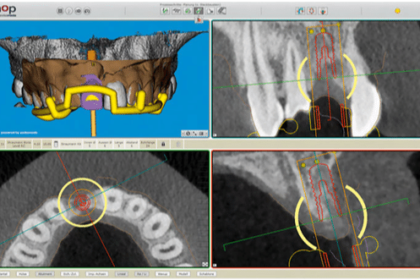

Au cours de ces dernières années, l’application clinique de la planification virtuelle d’opération guidée par gabarit est devenue un instrument d’insertion d’implants qui convient à la pratique. L’auteur de cet article exerce dans un cabinet privé en tant que spécialiste en chirurgie orale.

Il s’occupe du thème de l’«implantologie naviguée» depuis de nombreuses années et a été consulté lors du développement de plusieurs produits importants. Dans cet article, il souhaite exprimer son opinion sur les avantages qu’offre actuellement l’implantologie naviguée ainsi que sur les situations dans lesquelles il est préférable de choisir les méthodes conventionnelles.